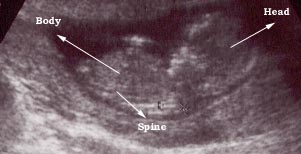

Photo Two

This is a nine weeks pregnancy as seen using a vaginal probe.